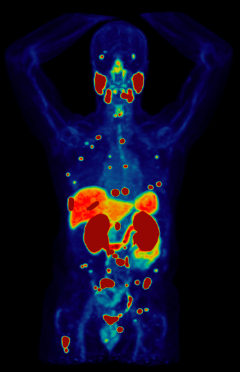

Certain radioisotopes emit radiation which is not harmful to cells and can be imaged using positron emission tomography (PET). This is the diagnostic part of theranostics. Others emit radiation which can damage and even kill cells. This is the therapeutic part.

In theranostics, doctors administer a specialized molecule called a radiotracer that can hold a radioisotope and target cancer cells. The radiotracer then binds to the cancer, allowing doctors to see exactly where it is and deliver cell-damaging radiation directly to it. This “see what you treat” approach helps doctors diagnose, stage, and treat cancer while minimizing damage to healthy tissues.

- Diagnostic Phase: To see where the cancer is, an imaging radiotracer will be administered by your health care team in our outpatient clinic. You will then undergo a full-body PET scan which will create pictures showing where the radiotracer goes. The whole process typically takes less than 3 hours, after which you can leave the clinic.